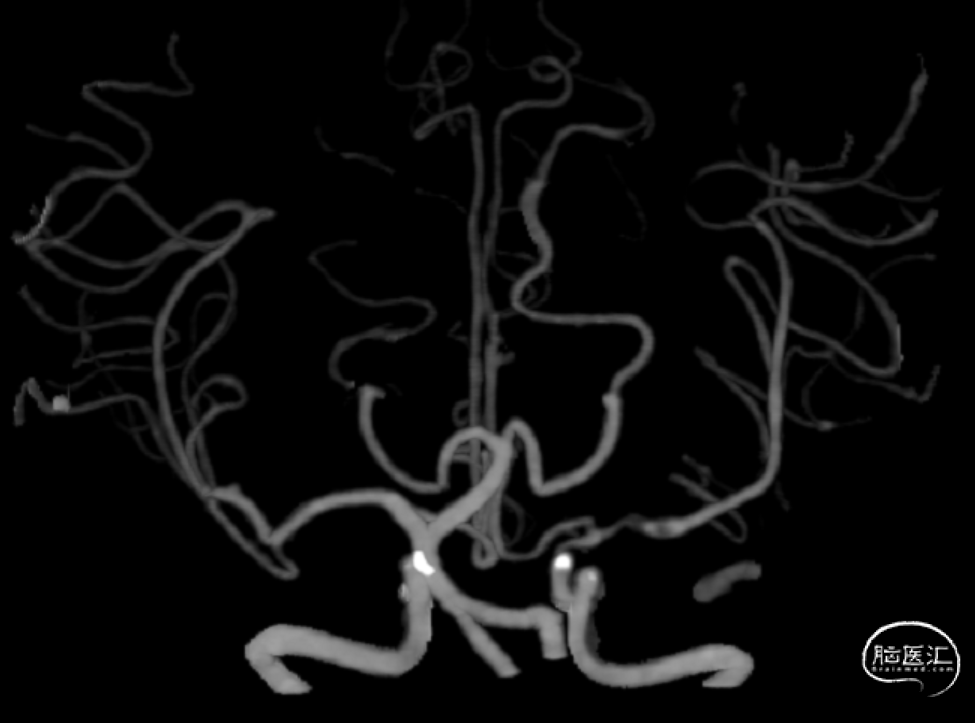

CTA:左侧颈内动脉C7段中度狭窄;左侧大脑中动脉M1段重度狭窄。

CTP:左侧大脑半球低灌注。

1、左侧大脑中动脉M1段重度狭窄,但未闭塞

2、CTP 低灌注I期:代偿期

3D:左侧颈内动脉C7段中度狭窄,左侧大脑中动脉M1段重度狭窄。